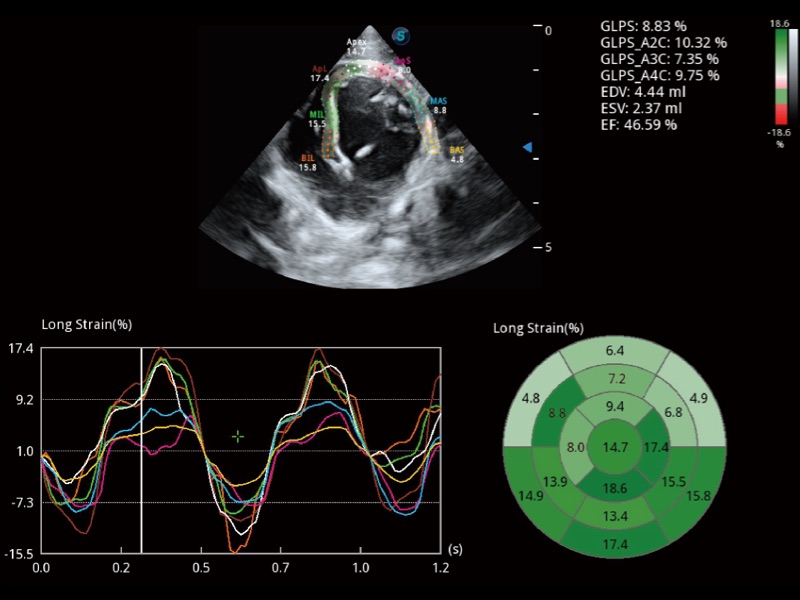

能夠基于左心室壁追蹤和辛普森法,自動計算射血分數(shù),支持多個可移動點描跡,與手動測量相比,極大節(jié)省了動物醫(yī)生的時間和精力。

實時用顏色表示心肌組織運動,觀察和定量組織的運動情況,對快速檢測與評估心肌的灌注和活性、電傳導(dǎo)及心肌收縮和舒張功能等均能提供重要的診斷信息。